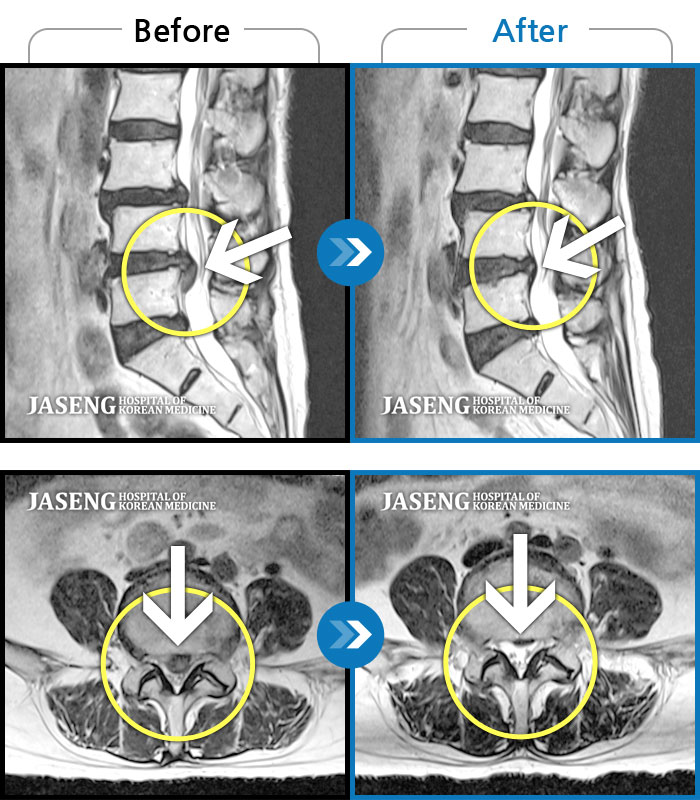

MRI 치료사례

왼쪽으로 골반과 엉덩이부터 발목까지 통증